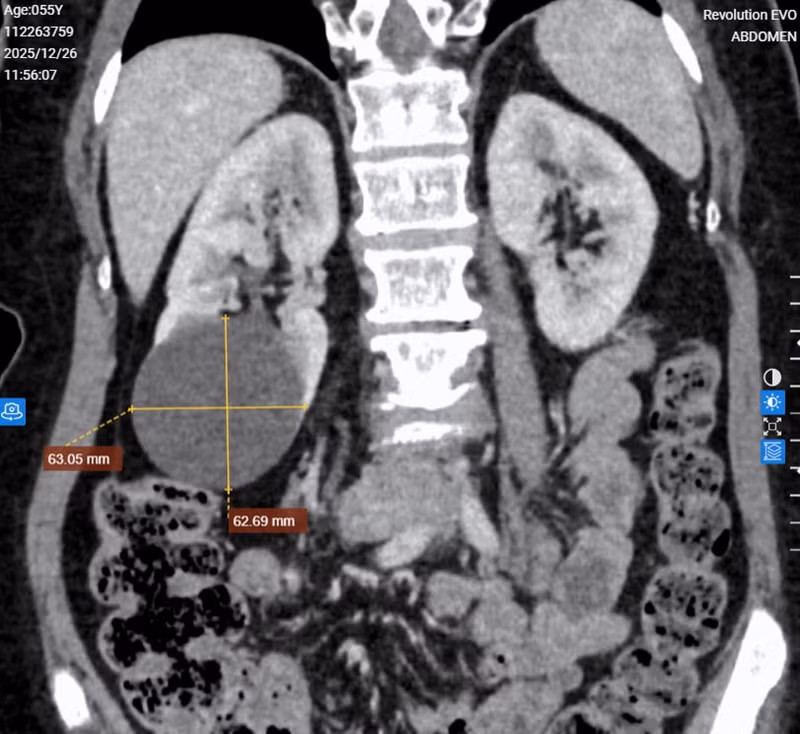

Chụp CLVT hệ tiết niệu cho thấy hình ảnh nang thận hai bên. Ảnh BV

Để làm rõ hơn hình ảnh nang thận cũng như đánh giá sự thông thương với đài bể thận, bác sĩ đã chỉ định chụp CLVT hệ tiết niệu. Hình ảnh cho thấy nang thận hai bên (phân loại Bosniak I - lành tính), trong đó thận phải có nang lớn không thông với đài bể thận.